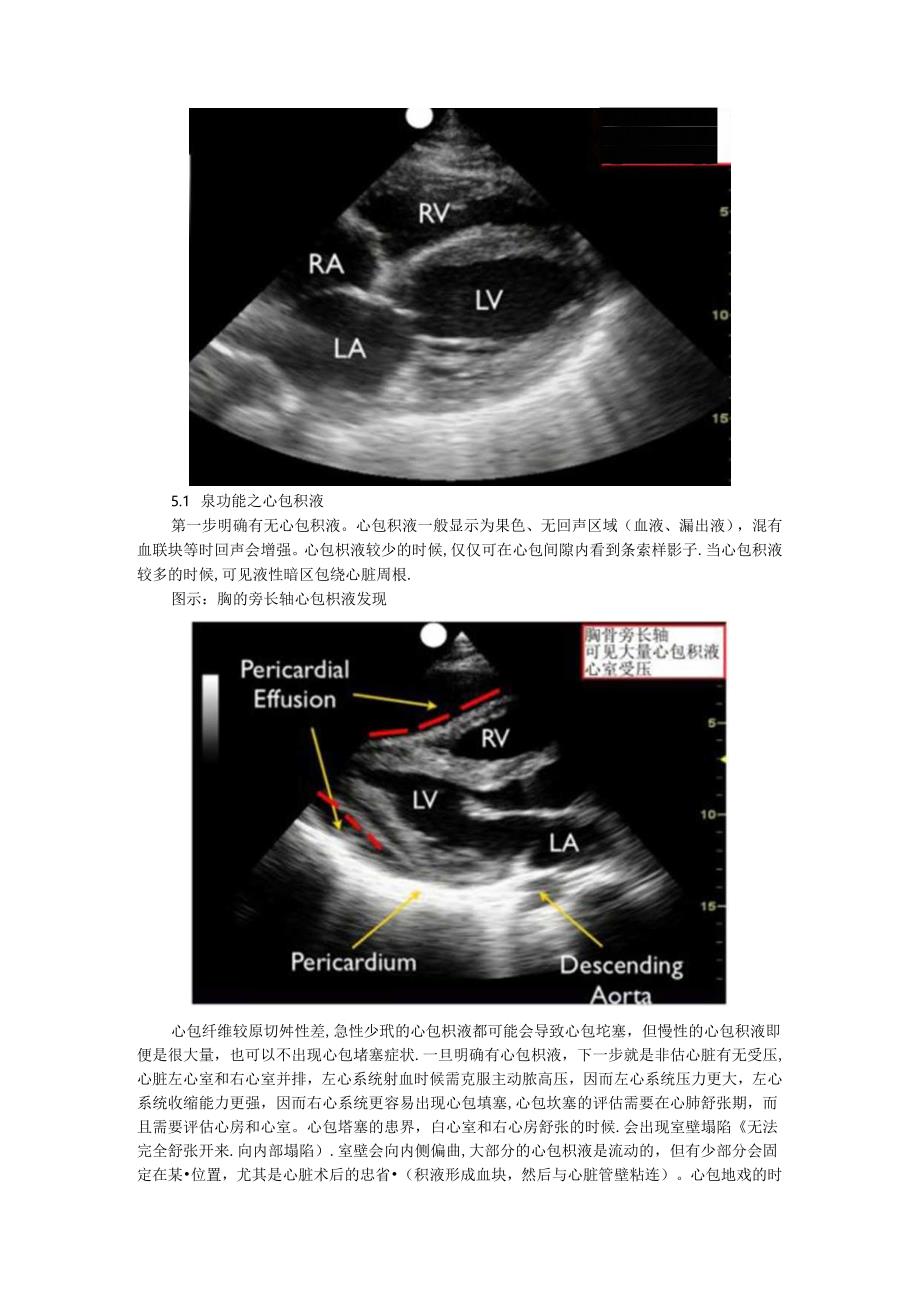

6、更分StIm克。更欲皆力。室小。靓t乏力三j:心鞋食曜里力GftW,。整X拿C融内拿冷石。室张力拳力QE或451力m)0跳依乏力依春*)Ffi!trt三0阳泄/失投方*下总寅大点,(口儿大量发内。0技击.艮大r1M第常晚征酒爱臭林P下鞍正*ut少!?程a(由-#)三aWftt正Ir正常胸骨旁切而在3、4肋间、胸骨左(.刽突下4腔心符探头放置在剑突下.并将探头朝向左肩.心尖四腔心需要患者左侧卧位,探头位于乳头平面、心脏搪动最强的地方.图示;制突下四腔心例突F4腔心深度15s!可见心脏增大5.1 泉功能之心包积液第一步明确有无心包积液。心包积液一般显示为果色、无回声区域(血液、漏出液),混有血联块

7、等时回声会增强。心包枳液较少的时候,仅仅可在心包间隙内看到条索样影子.当心包积液较多的时候,可见液性暗区包绕心脏周根.图示:胸的旁长轴心包枳液发现心包纤维较原切舛性差,急性少玳的心包枳液都可能会导致心包坨塞,但慢性的心包积液即便是很大量,也可以不出现心包堵塞症状.一旦明确有心包枳液,下一步就是非估心脏有无受压,心脏左心室和右心室并排,左心系统射血时候需克服主动脓高压,因而左心系统压力更大,左心系统收缩能力更强,因而右心系统更容易出现心包填塞,心包坎塞的评估需要在心肺舒张期,而且需要评估心房和心室。心包塔塞的患界,白心室和右心房舒张的时候.会出现室壁塌陷无法完全舒张开来.向内部塌陷).室壁会向内